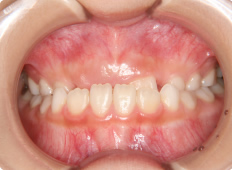

9歳女子

上下の前歯のギャップが大きい事と、下の前歯が上あごの歯肉に当たって痛む事を気にして来院されました。

下あごの成長が不足しているため、下あごが後方に位置しています。相対的に上顎前突の状態にあります。

下あごを前方へ成長させる装置を使って咬合状態を改善します。

【治療期間】

装置装着期間2年。

その後永久歯列完成まで成長経過観察を行いました。